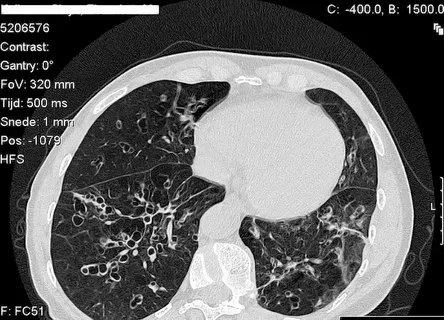

Genetic COPD illustrated in lung function test image